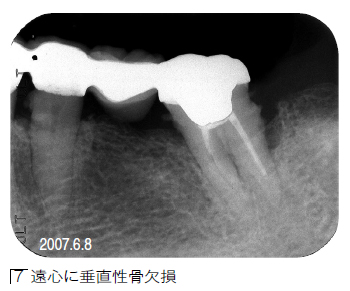

【デンタルX線写真の日付】![]() 誤:2007.6.8 正:2008.9.12 |